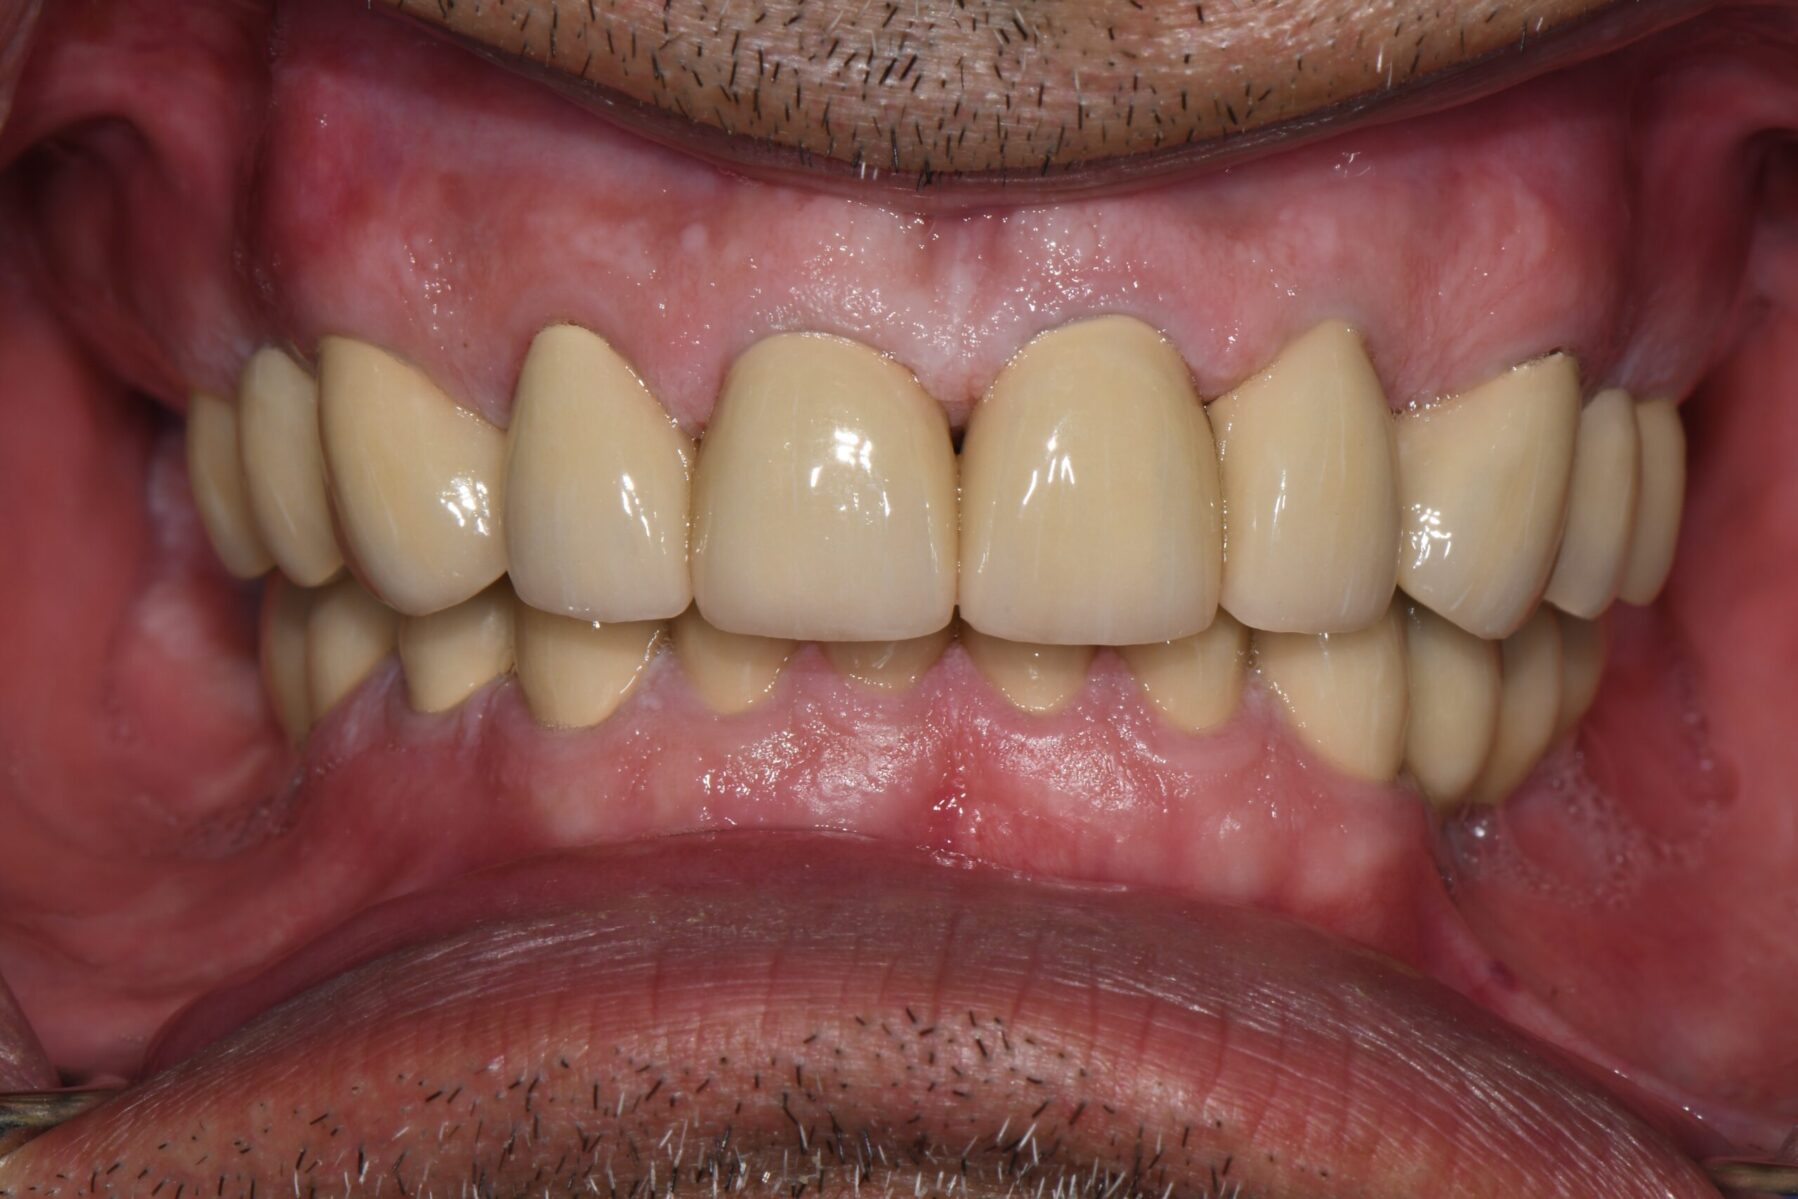

Full mouth rehabilitation encompasses a range of restorative dental procedures aimed at restoring the function, health, and esthetics of your entire mouth.

This may involve the use of crowns to protect and reinforce weakened teeth, dental implants to replace missing teeth, and veneers to improve the appearance of discolored or damaged teeth. Each treatment is tailored to match the color, shape, and size of your natural teeth, ensuring a cohesive and beautiful smile.